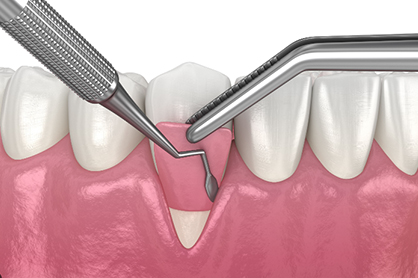

Minimally Invasive

- Our EXPERIENCE and METHOD give our patients faster RECOVERY time.

- Minimal Invasive Surgery